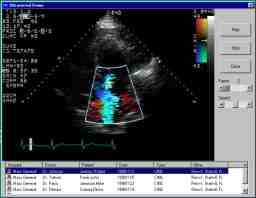

Problem: A manufacturer of cardiology imaging products asked us to develop a video acquisition system to replace an outdated 35mm cine film-based system used to capture images of the heart during catheterizations. The new system needed to provide physicians with the best possible image quality and archive years worth of images. It also needed to be easy and intuitive for lab technicians to operate, as well as robust enough to handle 24-hour-a-day, seven-day-a-week operation. In addition, the system needed to provide all sites with remote dial-up access to facilitate administration, image quality assessment and fault analysis. ![]() |

Solution: To meet these requirements, Bytes By Design developed a Windows NT-based system which acquires live X-ray video at 30 fps, compresses the loops and archives high-quality DICOM images to a massive ATM networked server. The GUI accepts patient demographics, displays system and network status and snapshots of the procedure. Recorded voice warnings reduce the possibility of errors. The remote administration client analyzes error logs, histograms images and reports error conditions. |